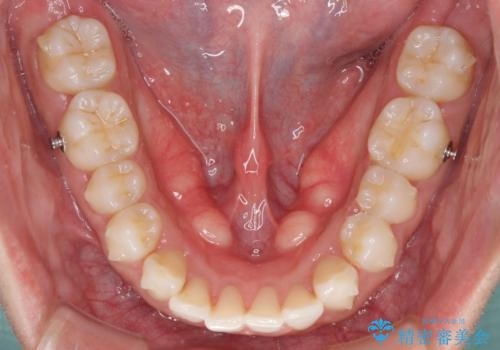

- 口の閉じにくさを気にして来院された患者様です。

患者様と相談の上、横顔の印象から抜歯矯正は必要ないと判断し、IPR(歯と歯の間)並びに歯列全体の後方移動により口元の突出感の改善することとしました。

しっかりと装着時間を守り、ゴムかけも徹底していただいたので、思いの外口元を引っ込めることができました。

これ以上の改善を望まれましたが、非抜歯矯正でこれ以上口元を引っ込めると食いしばりすやすい咬合となるため、この歯列で終了としました。